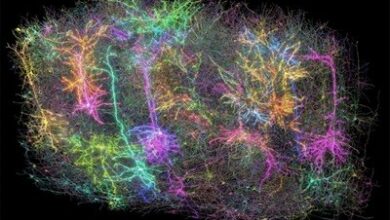

يجد العلماء كيفية توجيه إشارات الدماغ لأعلى أو لأسفل لعلاج الاضطرابات العقلية والعصبية

يقول العلماء إن رؤاهم الجديدة حول كيفية عمل بروتين رئيسي في الدماغ يمكن أن تساعد في حل سؤال طويل الأمد في علم الأعصاب الجزيئي. أفاد باحثون مدعومون من المعاهد الوطنية للصحة في جامعة جونز هوبكنز الطبية أنهم اكتشفوا هدفًا دوائيًا واعدًا يمكن أن يساعد في تنظيم نشاط بروتينات الدماغ الرئيسية. ومن خلال تعديل كيفية (…)